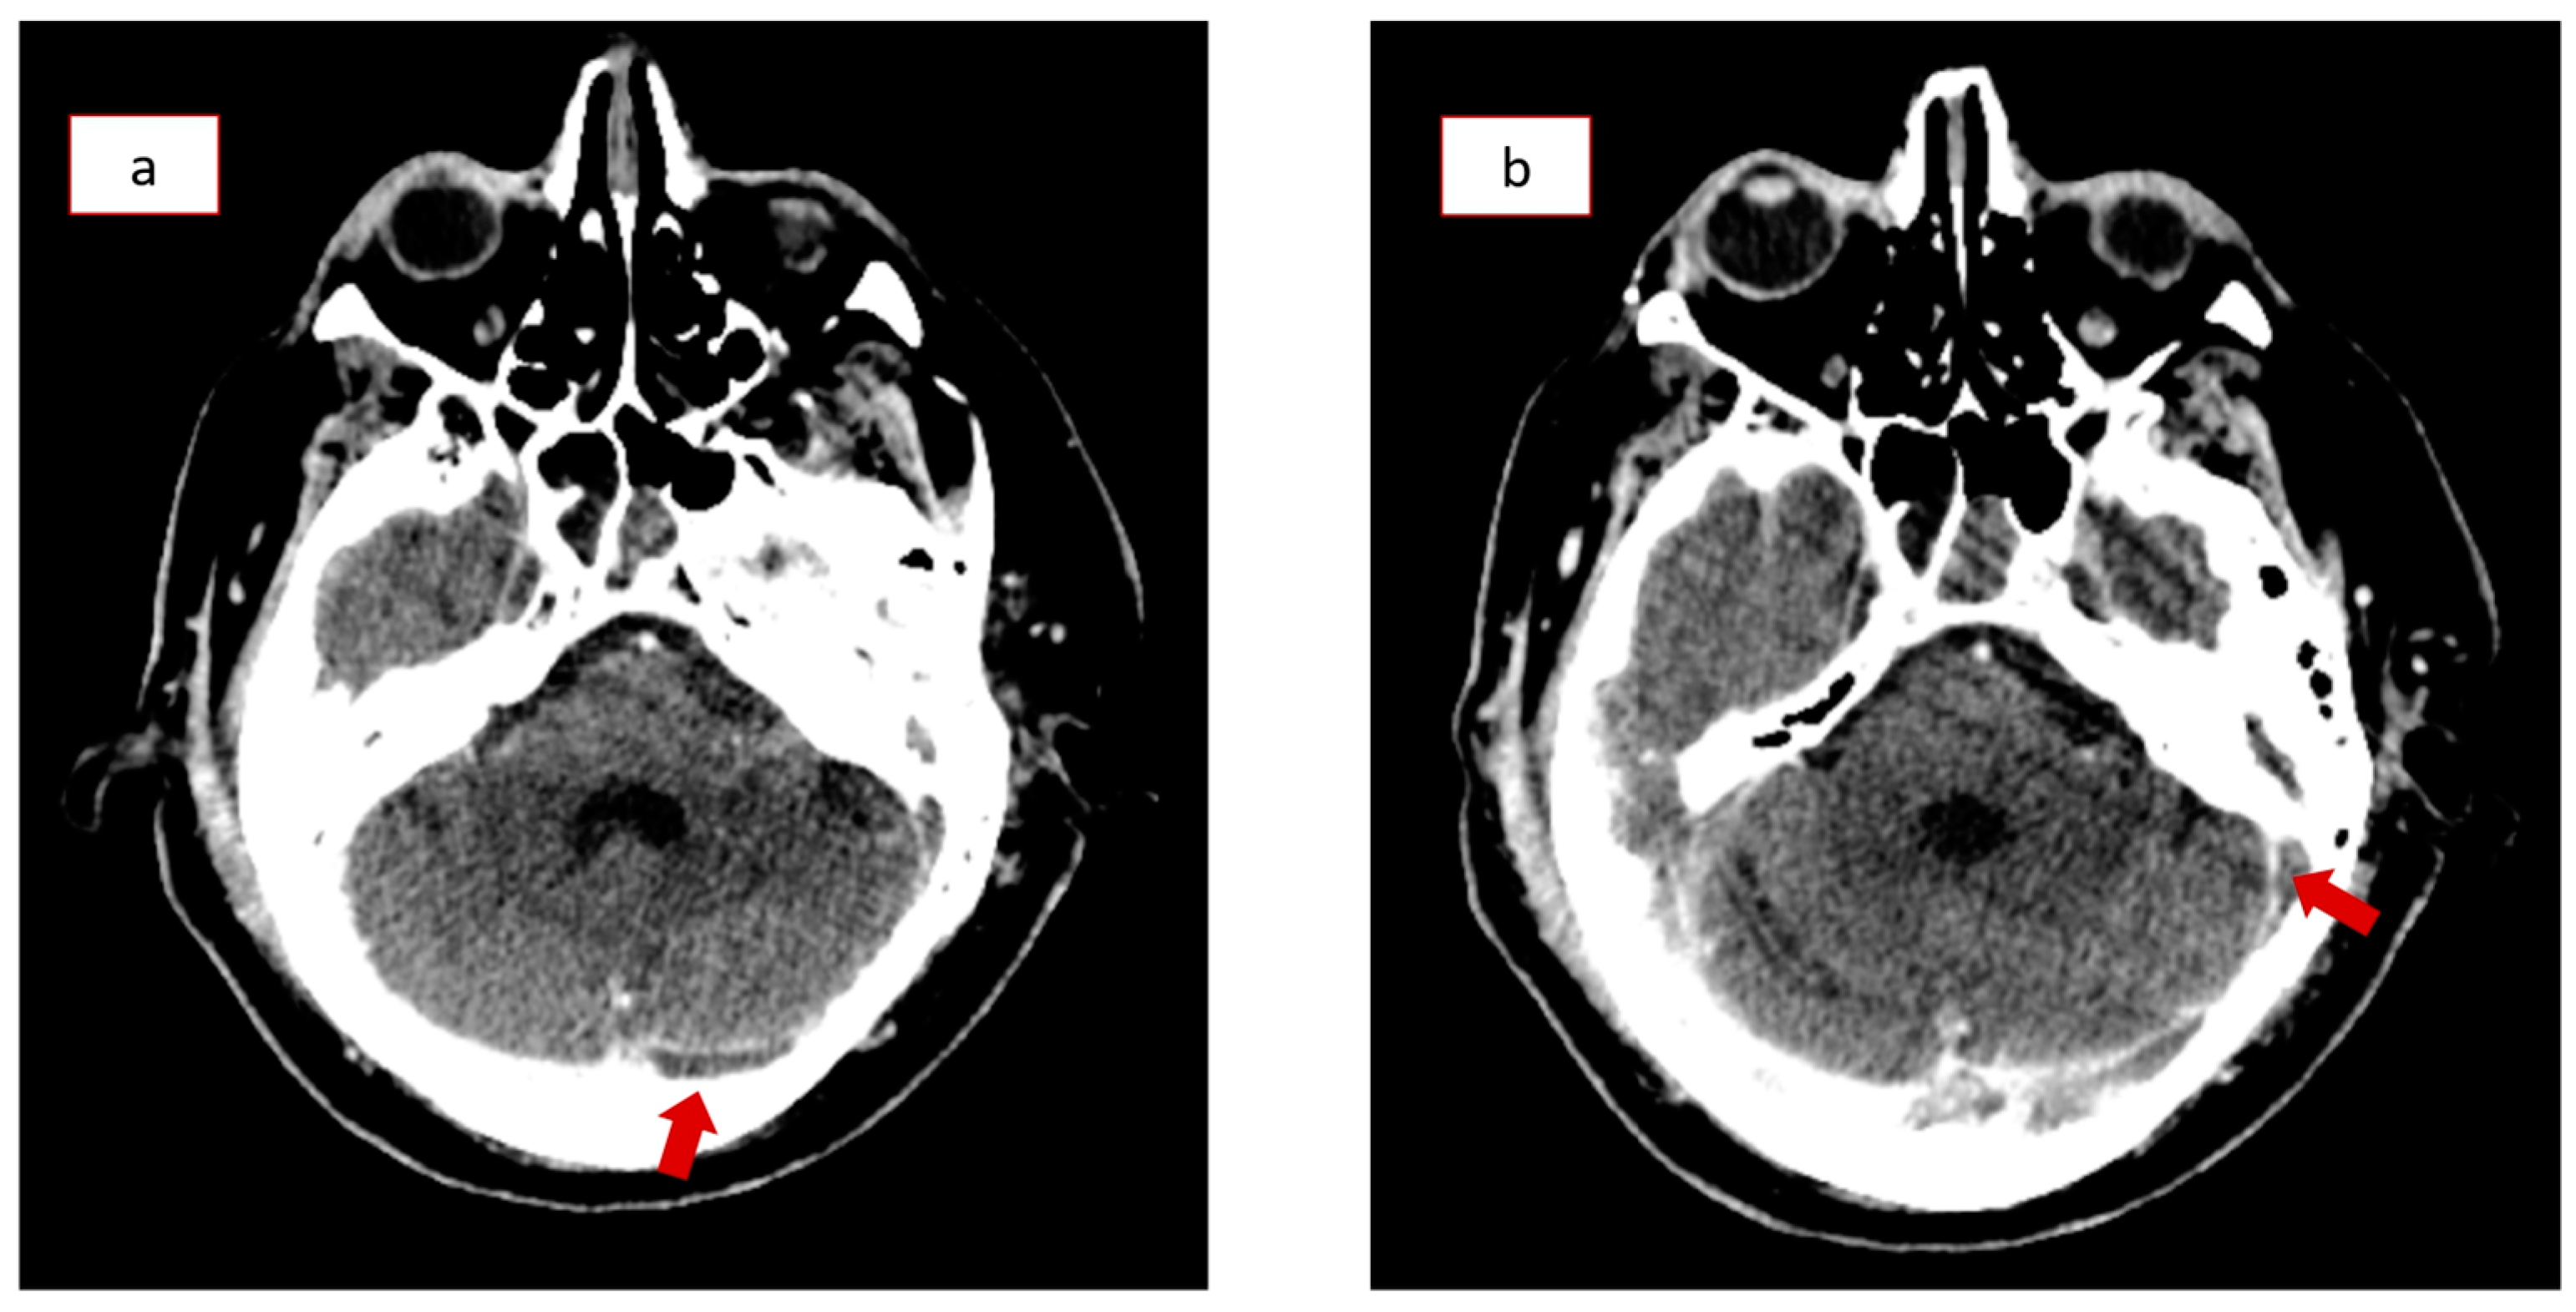

2. Case Presentation

3.4. Diagnosis and Radiological Findings